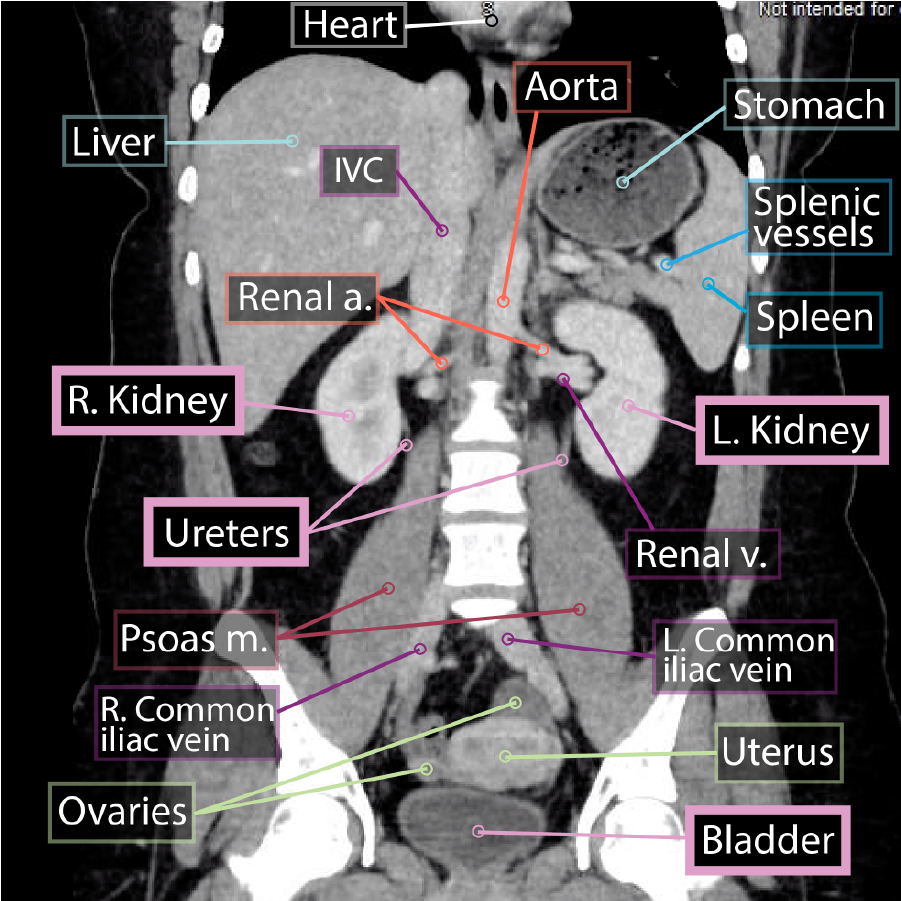

The ureters and urinary bladder are retroperitoneal structures in the abdomen and pelvis (some consider the urinary bladder to be subperitoneal or infraperitoneal).

The

kidneys lie on the posterior abdominal wall; these organs filter the blood and produce urine.